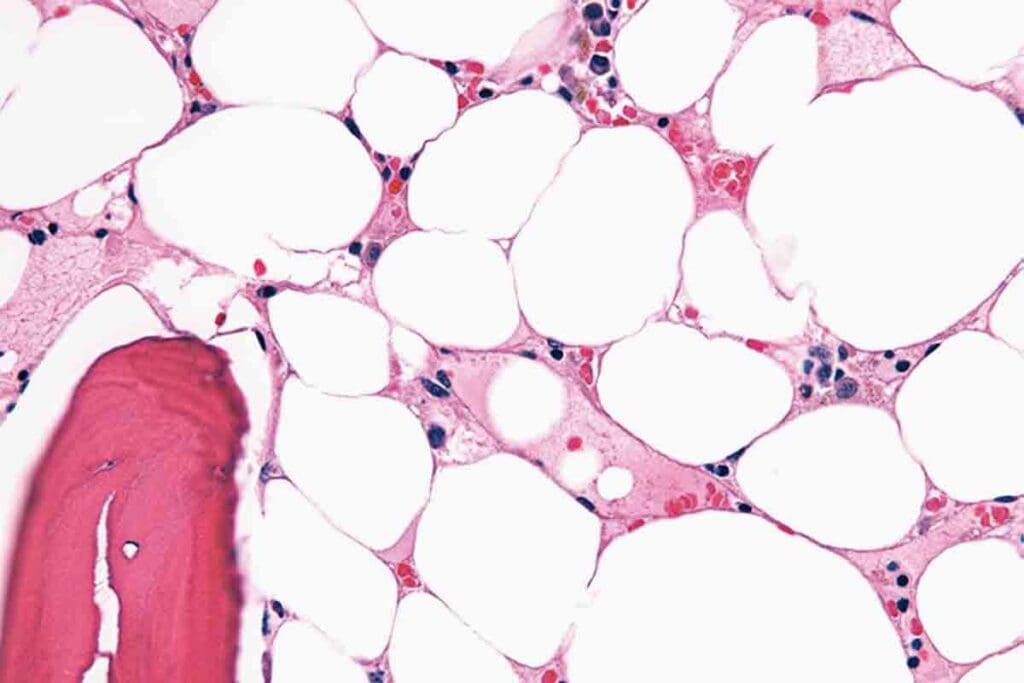

Hypocellular and Acellular Marrow Patterns

In aplastic anemia, the bone marrow shows hypocellular or acellular patterns. This means there’s a big drop in cell numbers. Studies show that how low the cell count is can tell us how severe the anemia is.

Increased Fat Spaces: A Characteristic Finding

One key sign of aplastic anemia is more fat in the bone marrow. As the blood-making cells drop, fat cells take their place. This is seen in biopsies and shows how the marrow is trying to adapt.

Residual Hematopoietic Islands

Even with low cell counts, some blood-making islands can be found. These islands hint at the marrow’s ability to recover. Knowing about these islands helps doctors predict how well a patient might do.

Bone Marrow Biopsy Techniques and Interpretation

Bone marrow biopsy is a key test for aplastic anemia. It lets doctors see how many cells there are and what they look like. It’s important to read these results well, as they help confirm the diagnosis and guide treatment.

The outlook for aplastic anemia depends on how bad it is and how well it responds to treatment. Knowing about the bone marrow’s state is key to choosing the right treatment and predicting how well a patient will do.